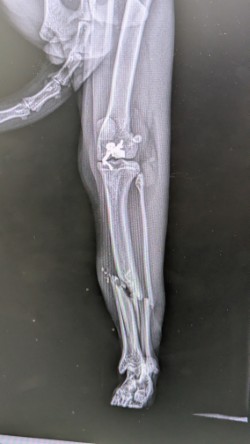

Leo’s owner rushed him to the emergency vets where they found three significant fractures to his right leg and the x-ray showed a bullet was lodged in his thigh. After careful assessment by the vet, it was determined that the only way forward was to amputate Leo’s injured leg from the hip joint.